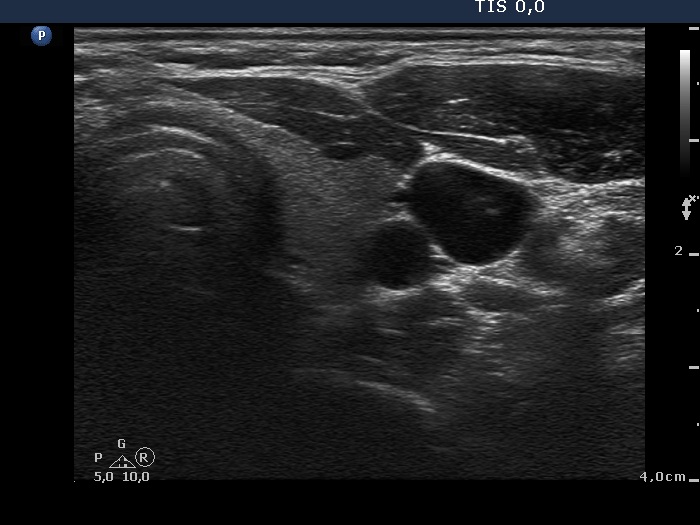

First examination (first and second row of images):

Clinical presentation: A 33-year-old woman was referred with typical complaints of subacute thyroiditis lasting for 6 weeks.

Palpation: Both lobes were hard and painful.

Functional state: moderate degree of hyperthyroidism with TSH-level 0.001 mIU/L, FT4 27.2 pM/L. Erythrocyte sedimentation rate was 49 mm/H, CRP was 9.2 mg/L.

Ultrasonography: The thyroid was hypoechogenic and inhomogeneous. The vascularization was average.

Cytological diagnosis: subacute, granulomatous de Quervain's thyroiditis.

Suggestion: steroid therapy for 6 weeks.